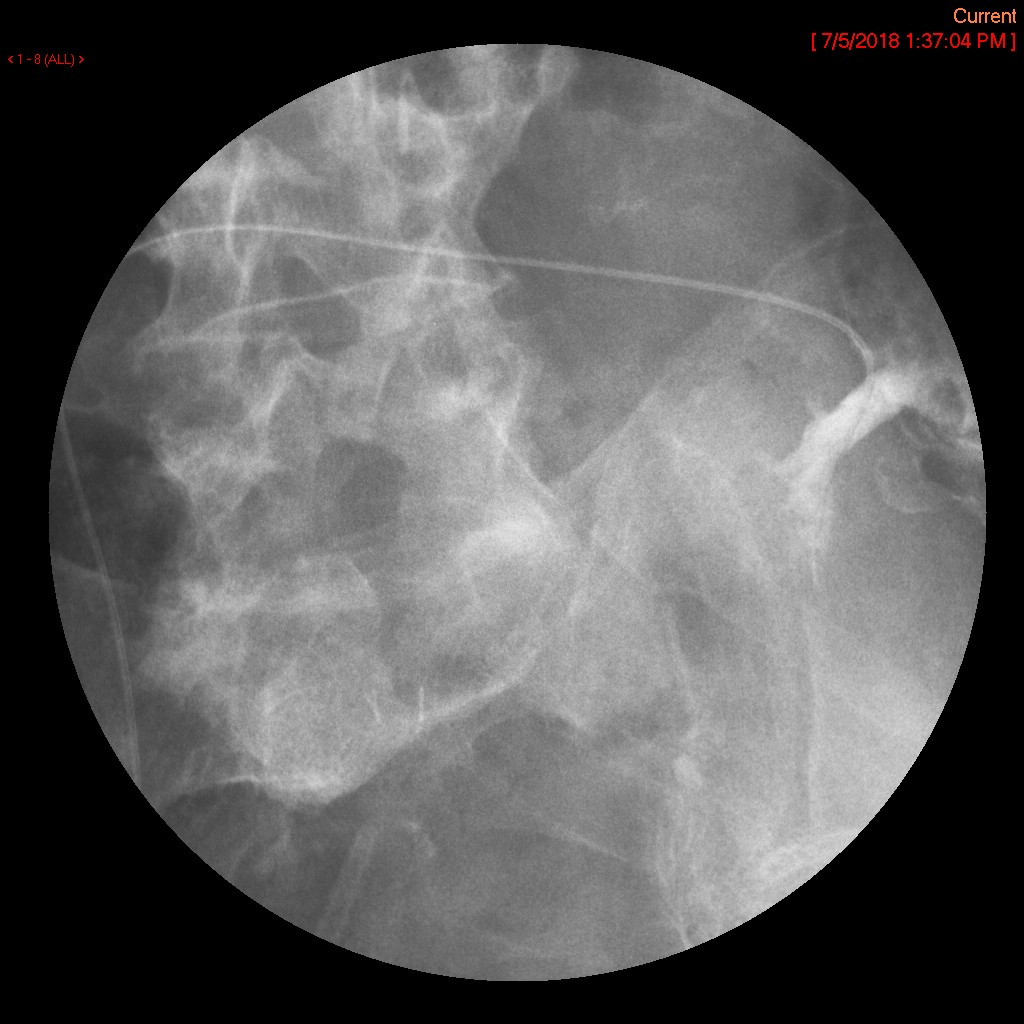

- The gynecologist will begin injecting contrast material into the uterus. Obtain images periodically throughout the procedure (usually at the direction of the gynecologist). The images should include the uterine cavity filled with contrast material, bilateral fallopian tubes filled with contrast material, and spillage and dispersion of contrast material into the peritoneal cavity (image 1) (image 2) (image 3) (image 4) (image 5).